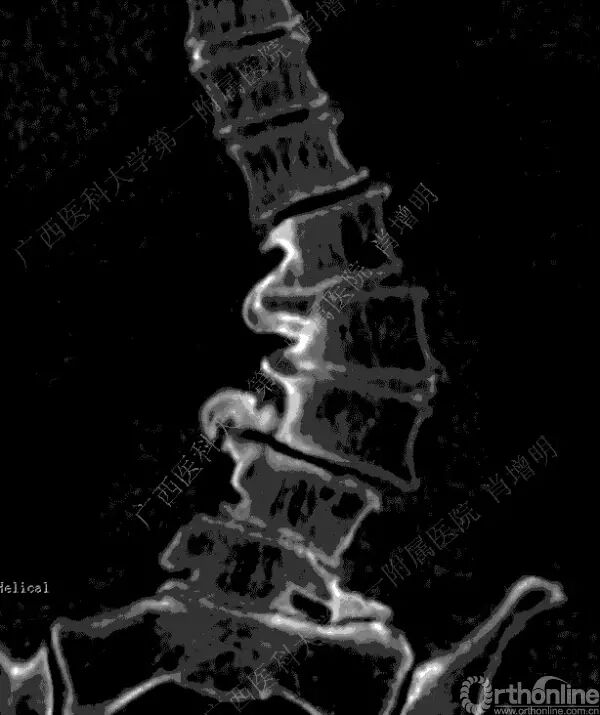

退变性脊柱侧凸是由于椎间盘退变后继发小关节退变,椎管和神经根管容积变化以及脊柱失稳,畸形等病理改变,以疼痛和神经压迫症状为主要表现的常见疾病。